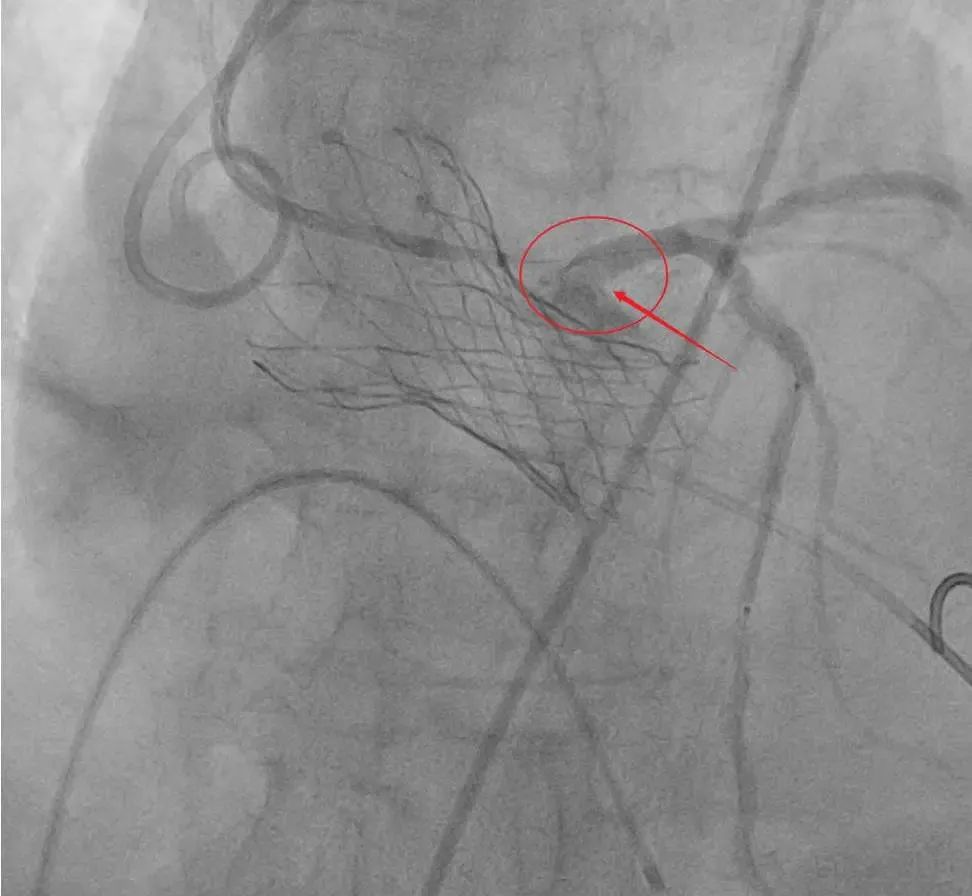

在充分的准备下,患者被推进了导管室。心内科团队首先通过球囊扩张技术预判冠脉血流情况,随后在冠脉开口处预埋支架作为“保护伞”,防止瓣膜释放时堵塞血管。由于患者心脏呈横位且钙化严重,心内科团队借助圈套器牵引调整角度,最终成功将人工瓣膜精准植入。术后超声显示,新瓣膜形态完美,血流动力学显著改善,冠脉支架保护下的血管通畅无阻。

▲释放冠脉烟囱支架

▲最终结果